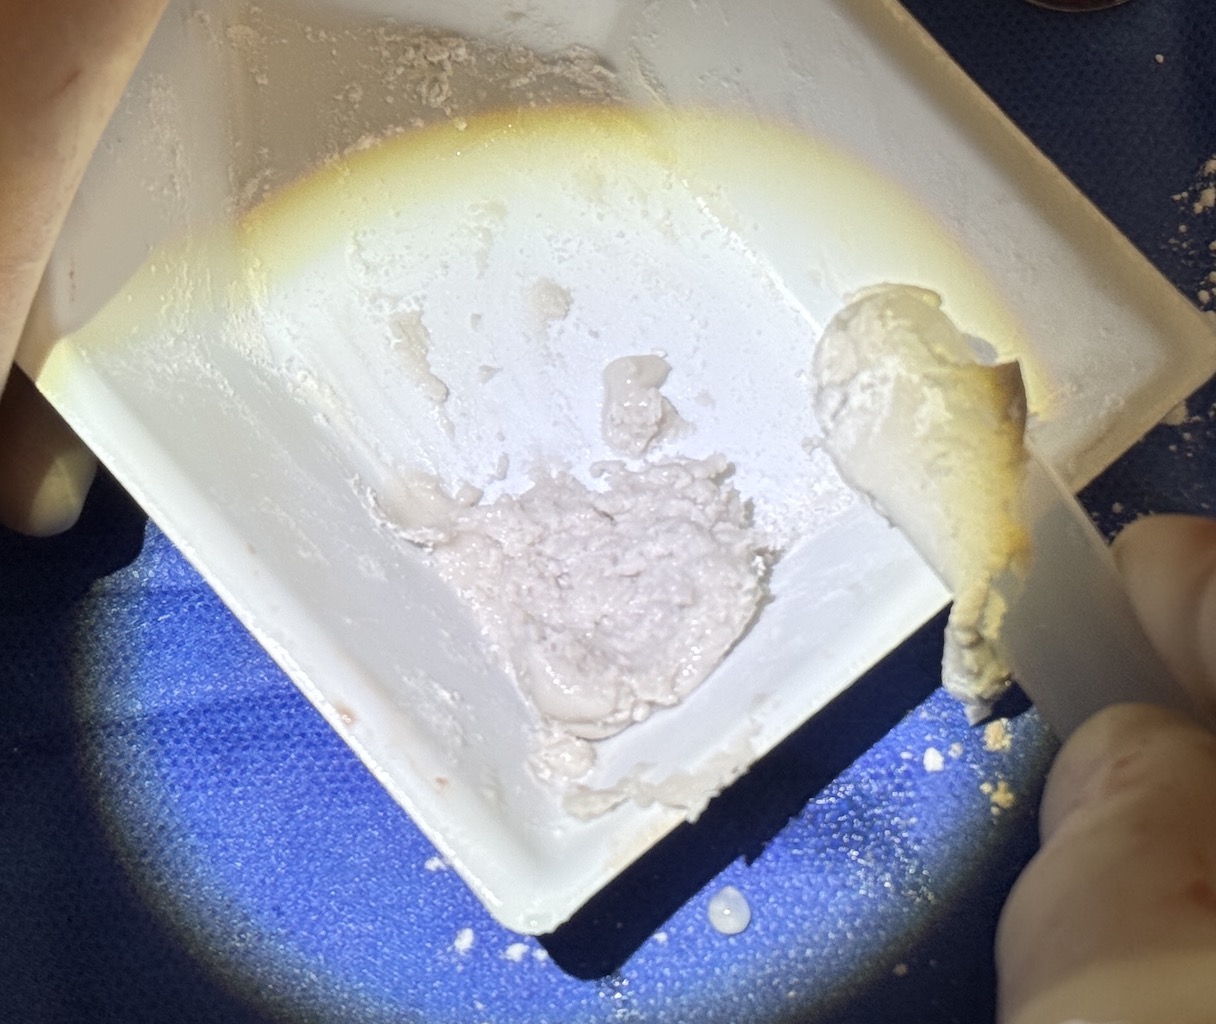

Desire for young patient to have a rounder back of his head with congenital plagocephaly

Right occipital skull augmentation using hydroxyapatite cement. (because he was a young growing patient)

Desire for young patient to have a rounder back of his head with congenital plagocephaly

Right occipital skull augmentation using hydroxyapatite cement. (because he was a young growing patient)